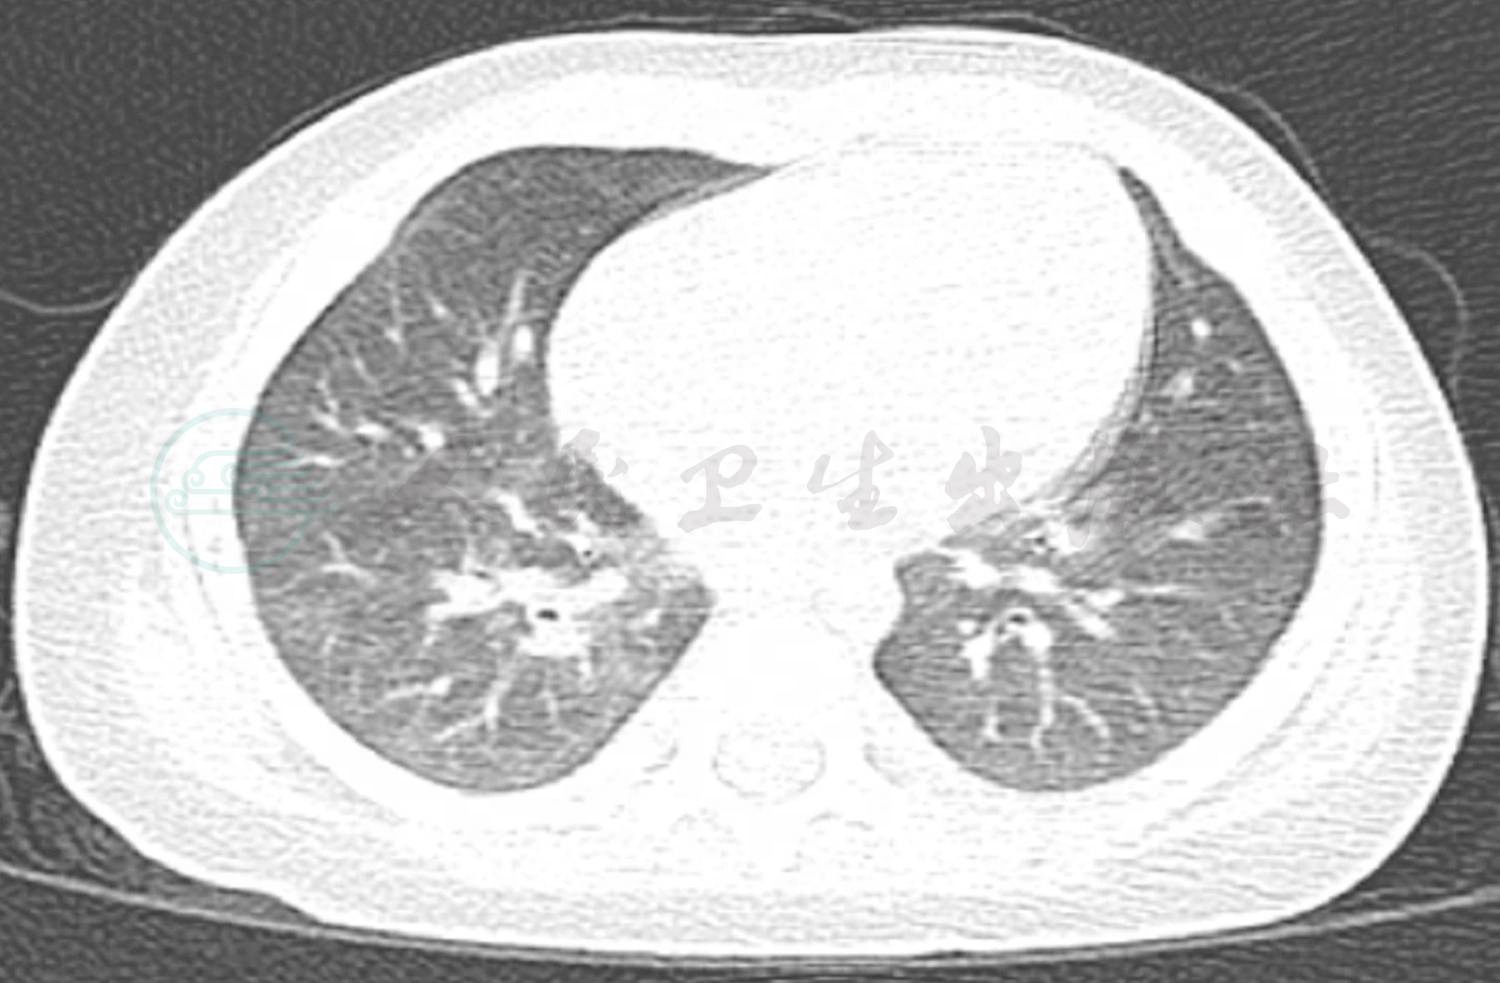

辅助检查:门诊血常规:WBC 12.1×109/L,NE 70%;RBC 3.9×1012/L,HGB 110g/L;PLT 206×109/L。门诊肺 CT(图3):双肺纹理增粗模糊,左肺上叶占位性病变。胸腔彩超:左侧胸腔腋后线第2、3肋间可见2.4cm×2.7cm液性暗区,内可见点片状回声。

图3 笔者医院门诊肺CT结果

入院后完善相关检查:血常规:WBC 12.1×109/L,提示白细胞升高,以中性粒细胞为主;CRP 11.5mg/L(0~8mg/L);PCT 0.45ng/L(<0.05ng/L),ASO<25.0(0~200U/ml);ESR 12mm/h,均正常;病原学检测除肺炎支原体抗体(MPAb)1:40外,肺炎支原体抗体-IgM(MPAbIgM)阴性、鼻咽拭子肺炎支原体DNA测定阴性,肺炎衣原体抗体-IgM、常见呼吸道、肠道病毒及肝炎病毒检测均阴性。免疫球蛋白及淋巴细胞亚群均正常,除外免疫缺陷病。总IgE 38U/ml正常。尿便常规、肝肾功能、血气分析均正常。心电图正常,心脏、肝胆脾及肾脏彩超未发现异常。胸片(图4):双肺纹理增粗模糊,左肺上叶实变影,结合原有肺CT结果诊断急性支气管肺炎,左肺占位性质待定。考虑存在细菌感染,给予静脉滴注头孢呋辛钠100mg/(kg·d)抗感染,予祛痰止咳药物对症治疗。随后继续完善相关检查:血细菌培养未见细菌生长,痰细菌涂片及细菌培养为呼吸道正常菌群,真菌涂片及培养均阴性。结核抗体(TBAb)、结核菌素试验阴性,T-spot阴性,无结核感染依据。仅1,3-β葡聚糖23pg/ml略高,不除外真菌感染。头孢呋辛抗炎3天体温未见明显下降,升级抗生素至头孢吡肟后体温逐渐下降,咳嗽、喘息症状及肺部湿啰音及喘鸣音逐渐减轻,入院第10天体温恢复正常,仍有咳嗽及间断喘息;入院第15天,行肺CT+三维重建(图5)提示原有肺实变区液化、坏死,出现空腔阴影形成“新月形空气征”。入院第17天行纤维支气管镜检查(图6),结果:左、右肺各叶、段、亚段开口位置正常,黏膜充血、少许浆液性分泌物。除外先天性气道发育异常。BALF检查:一般细菌、结核菌及真菌涂片检查均未找到相应阳性菌,细菌培养未见细菌生长,PCR-TB阴性,真菌培养:25℃黑曲霉生长。追问病史:患儿有长期潮湿生霉环境接触史。诊断为曲霉菌肺炎(侵袭性肺曲霉菌病)。加用伊曲康唑口服[6~8mg/(kg·d)]、两性霉素B雾化吸入(2.5mg/次,2次/d)1周,咳嗽逐渐减轻,喘息症状及肺部喘鸣音消失后出院。